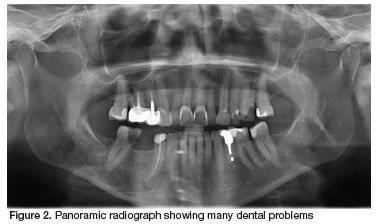

A patient presented to a new dentist seeking treatment. Before even taking the time to listen to her main complaint, establish her desires, or examine her mouth, the clinician began to discuss her "ugly front teeth", and the need to have all six anterior maxillary teeth crowned to give her a "beautiful smile" (Figure 1). The patient was rather disconcerted, as she had never been too worried about her smile, and was seeking relief from the severe pain she had been experiencing in the 4th quadrant. The dentist then decided it might be prudent to take a radiograph and investigate further. An orthopantomogram (Figure 2) revealed several dental problems, the most obvious being the large carious lesion on the 46. The patient was told that this tooth could be restored if she was willing to undergo a root canal therapy and pay for a seventh crown. If not it could be extracted immediately while the follow-up visits were being scheduled.